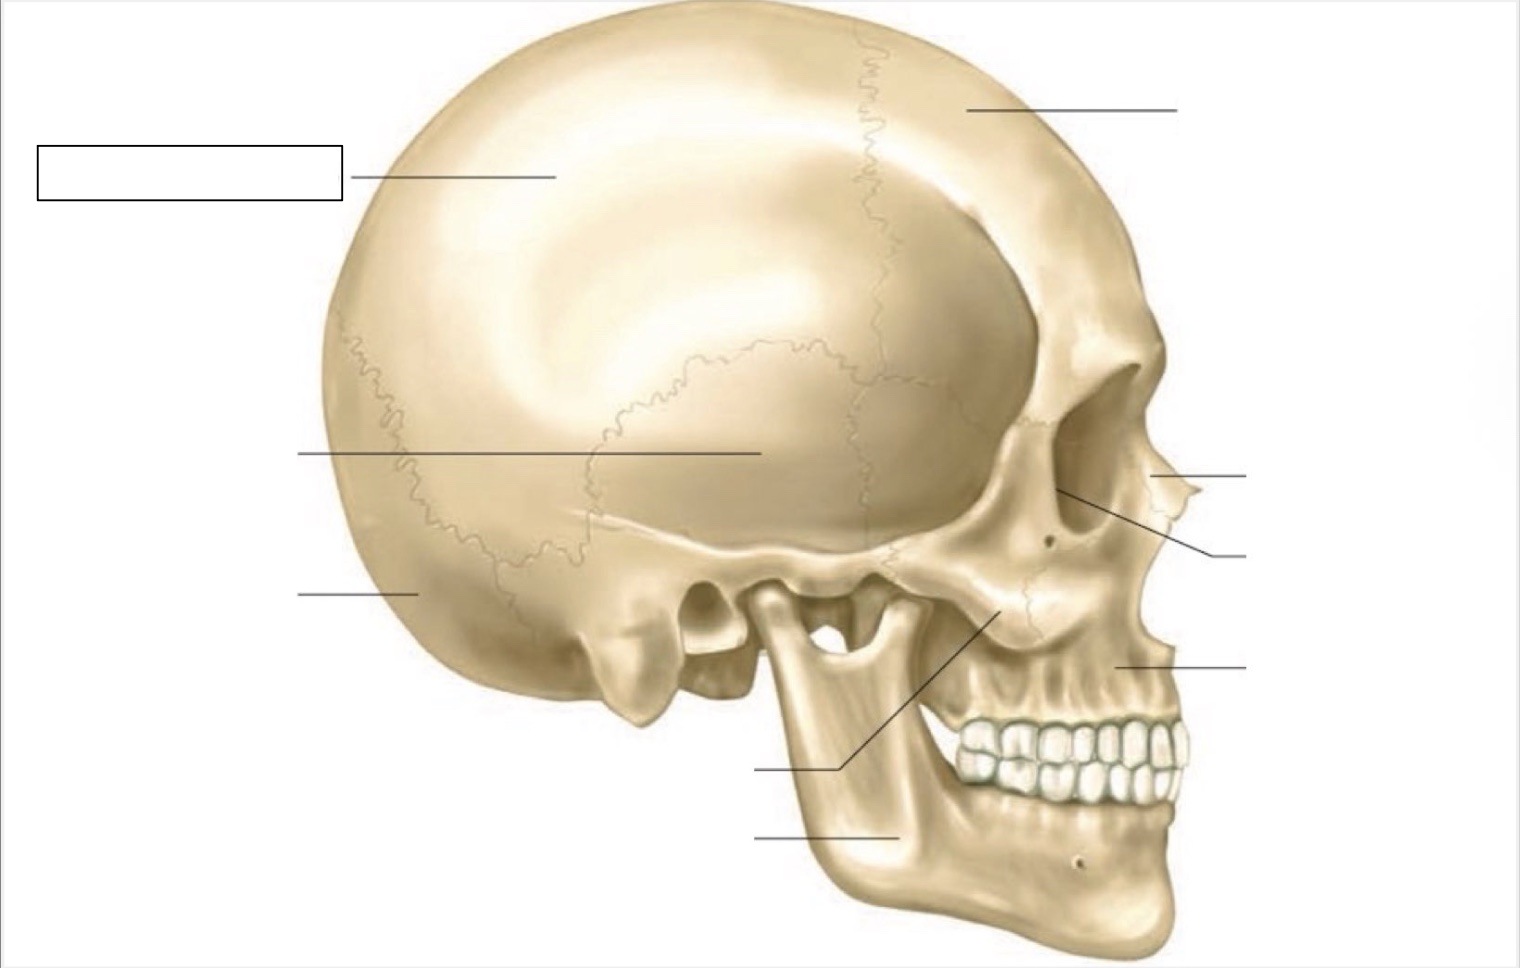

skull

frontal bone

nasal bone

orbit

maxilla

mandible

zygomatic bone

occipital bone

temporal bone

parietal bone